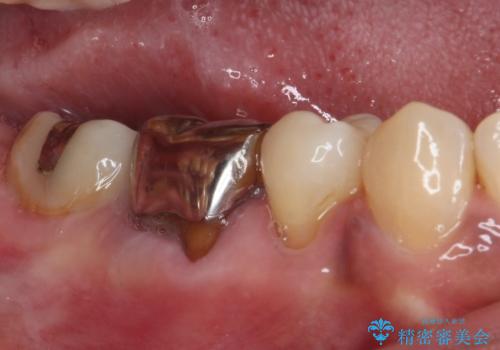

ゴールドは「白い歯」ではありませんが、銀歯の金属色とは異なり、非常にきれいな色合いが特徴です。

もちろん、適合が極めて良いという圧倒的メリットもゴールドクラウンやゴールドインレーの特徴です。